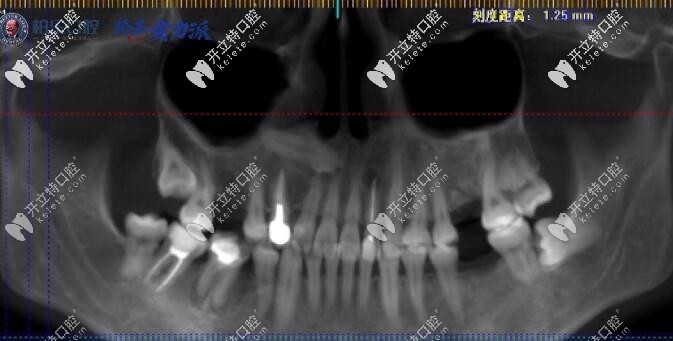

牙齒情況:凸嘴、齙牙、骨性下巴后縮

矯正方案:拔除4顆4號(hào)牙

她的情況屬于上頜骨前突,下頜骨骨性后縮還伴隨著齙牙,整體呈凸面型,所以給他拔除4顆4號(hào)牙,戴隱適美牙套推磨牙后移整體牙根往里面收,還有就是牙套臉并不是牙套造成的,是因?yàn)槟挲g大了以后,脂肪流失造成的。